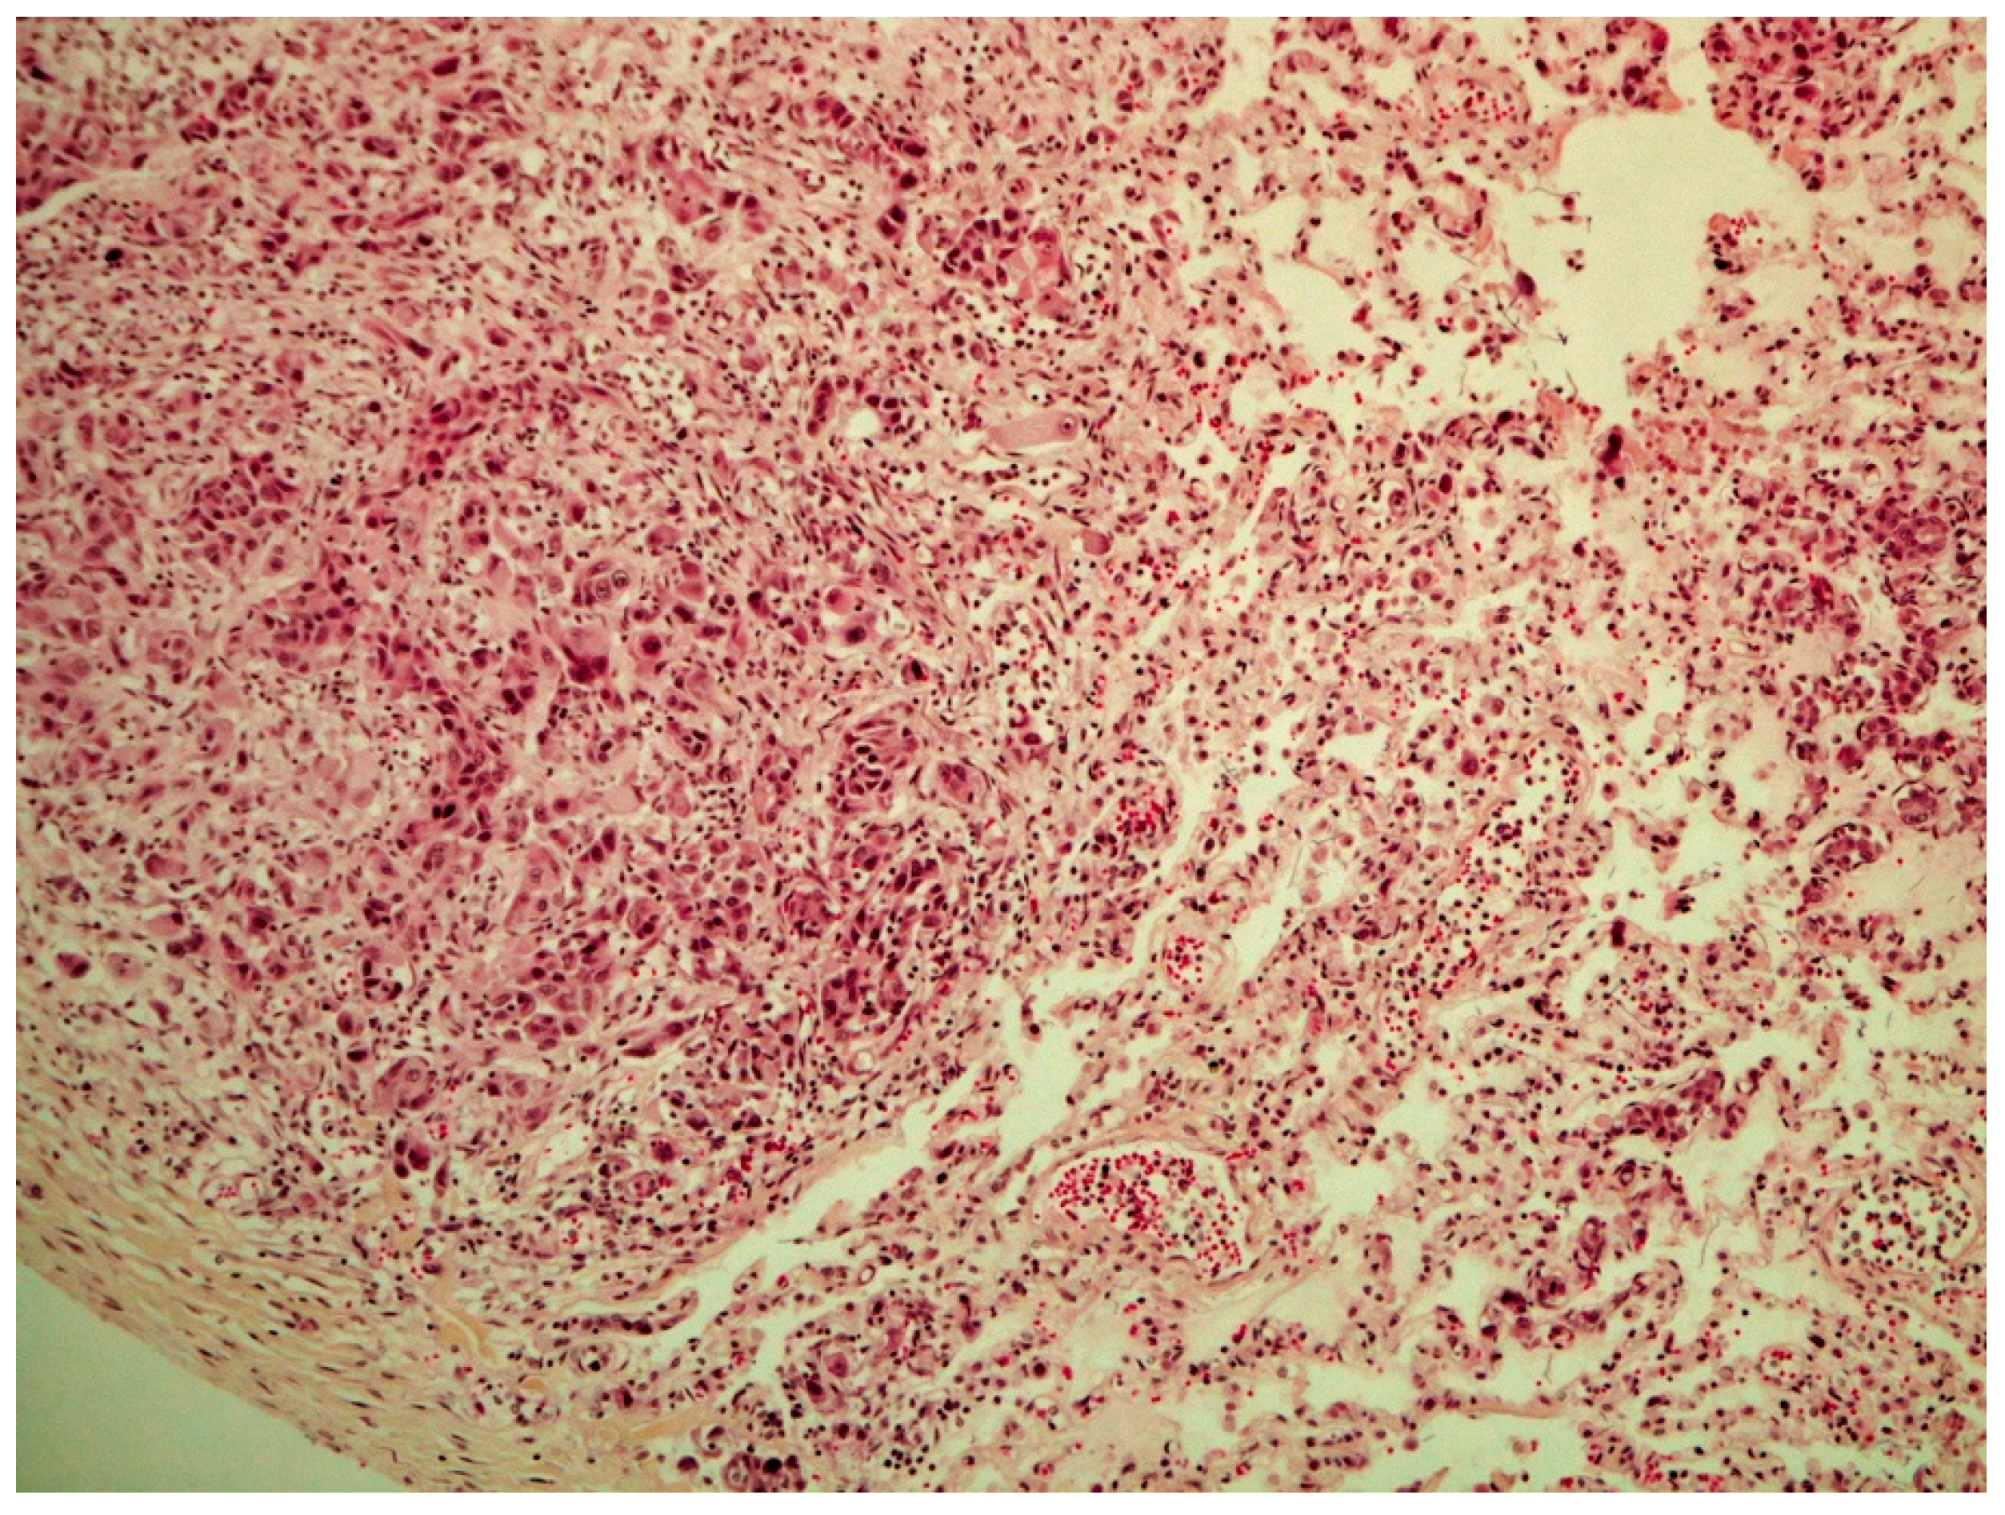

On histological examination (HES stain ×40) (Figure 4), the prostate was invaded and replaced by a poorly defined infiltrative unencapsulated and densely cellular tumor. Tumoral population was arranged in multiple lobules of duct-like structures, lined by unique or multiple layers of pleomorphic neoplastic cells, or occasionally in small clusters of neoplastic cells separated by a plentiful stroma response. Metastatic emboli were numerous. Multiple pulmonary emboli and focal metastatic infiltration with carcinomatous cells (HES stain ×100) (Figure 5) confirmed the severe lymphatic and parenchymatous pulmonary tumor extension, which probably caused the hypertrophic osteopathy. A decalcified longitudinal femur section (HES stain ×40) (Figure 6), showed, from right to left, the cortex, perpendicular bony periosteal trabecular proliferation and an exuberant periosteal reaction characteristic of hypertrophic osteopathy lesions. In addition, several concomitant foci of carcinomatous cells were observed in the medullary cavities of the preexisting bone and in the periosteal proliferation (HES stain ×40) (Figure 7). These observations confirmed the diagnosis of prostatic adenocarcinoma with lymph node, pulmonary, liver and bone metastases, associated with hypertrophic osteopathy.

Figure 5. Multiple pulmonary emboli and focal metastatic infiltration of carcinomatous cells (HES stain ×100).